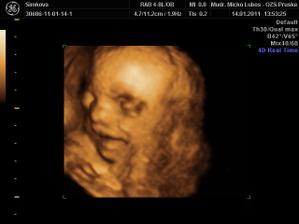

Naša princezná (v brušku...)

Stráááášne sa na ňu tešíme.......

je to mala herecka....ukazala nam vsetko....moc sa na nu uz tesime